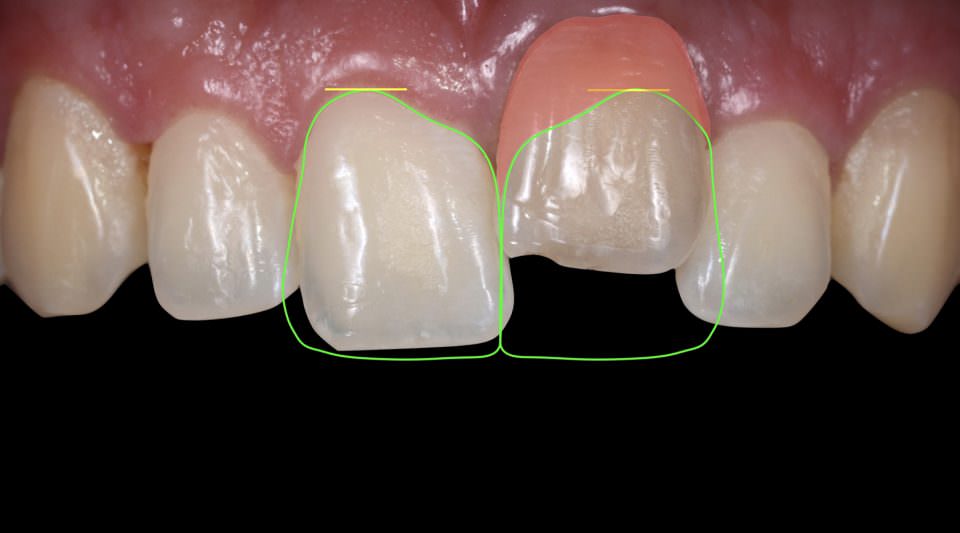

آنکیلوز دندان اغلب با ویژگی های بالینی مشخص ظاهر می شود. برجسته ترین علامت دندان فک جوش عدم تحرک طبیعی دندان است، زیرا دندان ذوب شده توانایی حرکت در حفره خود را ندارد.دندان فک جوش می تواند منجر به تراز نامناسب و انسداد دندان های مجاور شود. در برخی موارد، آنکیلوز دندان ممکن است منجر به تغییرات قابل توجهی در ظاهر ناحیه آسیب دیده شود، مانند کوتاهتر ظاهر شدن دندان یا عدم رویش کامل دندان؛ در مواردی نیز دیده شده است، به دلیل اینکه دندان انکیلوز شده رویش نمییابد، تعداد دندانهای بیمار از یک فرد عادی کمتر خواهد بود و نیروی کمتری به دندانهای فک مقابل وارد میشود. به همین دلیل هم دندانهای فک مقابل ممکن است کمی بیرونتر از حالت معمول دیده شوند.

2.زیبایی: دندان های انکیلوز که نمی توانند رویش پیدا کنند می توانند باعث نگرانی های زیبایی شوند و بر تقارن و ظاهر لبخند تأثیر بگذارد.